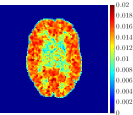

Figure 4, Figure 5, and Figure 6 show the mean images computed over the ten reconstructions obtained by the methods reg-AS-TR, reg-GN, and by the Matlab routine lsqcurvefit implementing a standard Trust-Region-Reflective least-squares algorithm [11, 10]. We used the noise-free IF and the perturbed IF with and of noise, respectively. Figure 7 contains mean and standard deviation values of the kinetic parameters computed over the ten reconstructions and over each one of the four homogeneous regions, for each one of the three noise levels on the IF.

In general, reg-AS-TR and lsqcurvefit seem to provide similar mean reconstructions, although uncertainties associated to lsqcurvefit are significantly bigger. On the other hand reg-GN seems to systematically underestimate the parameter values within region . Furthermore and as expected, for all methods the quality of the parametric reconstructions deteriorates with increasing noise levels; this is more clear from the and parametric images, probably due to the different sensitivities of the data with respect to the model parameters [37]. In reg-GN and lsqcurvefit some artifacts can be observed at the edges of the homogeneous regions, especially around region and region , whereas the effect of regularization in reg-AS-TR results in a reduced presence of artifacts while the structure of the regions is preserved. This general trend is confirmed by the error-bar plots of Figure 7. Finally, the frames in Figure 8 corresponding to reg-AS-TR show a significant improvement of the image quality with respect to what is provided by the other two approaches.